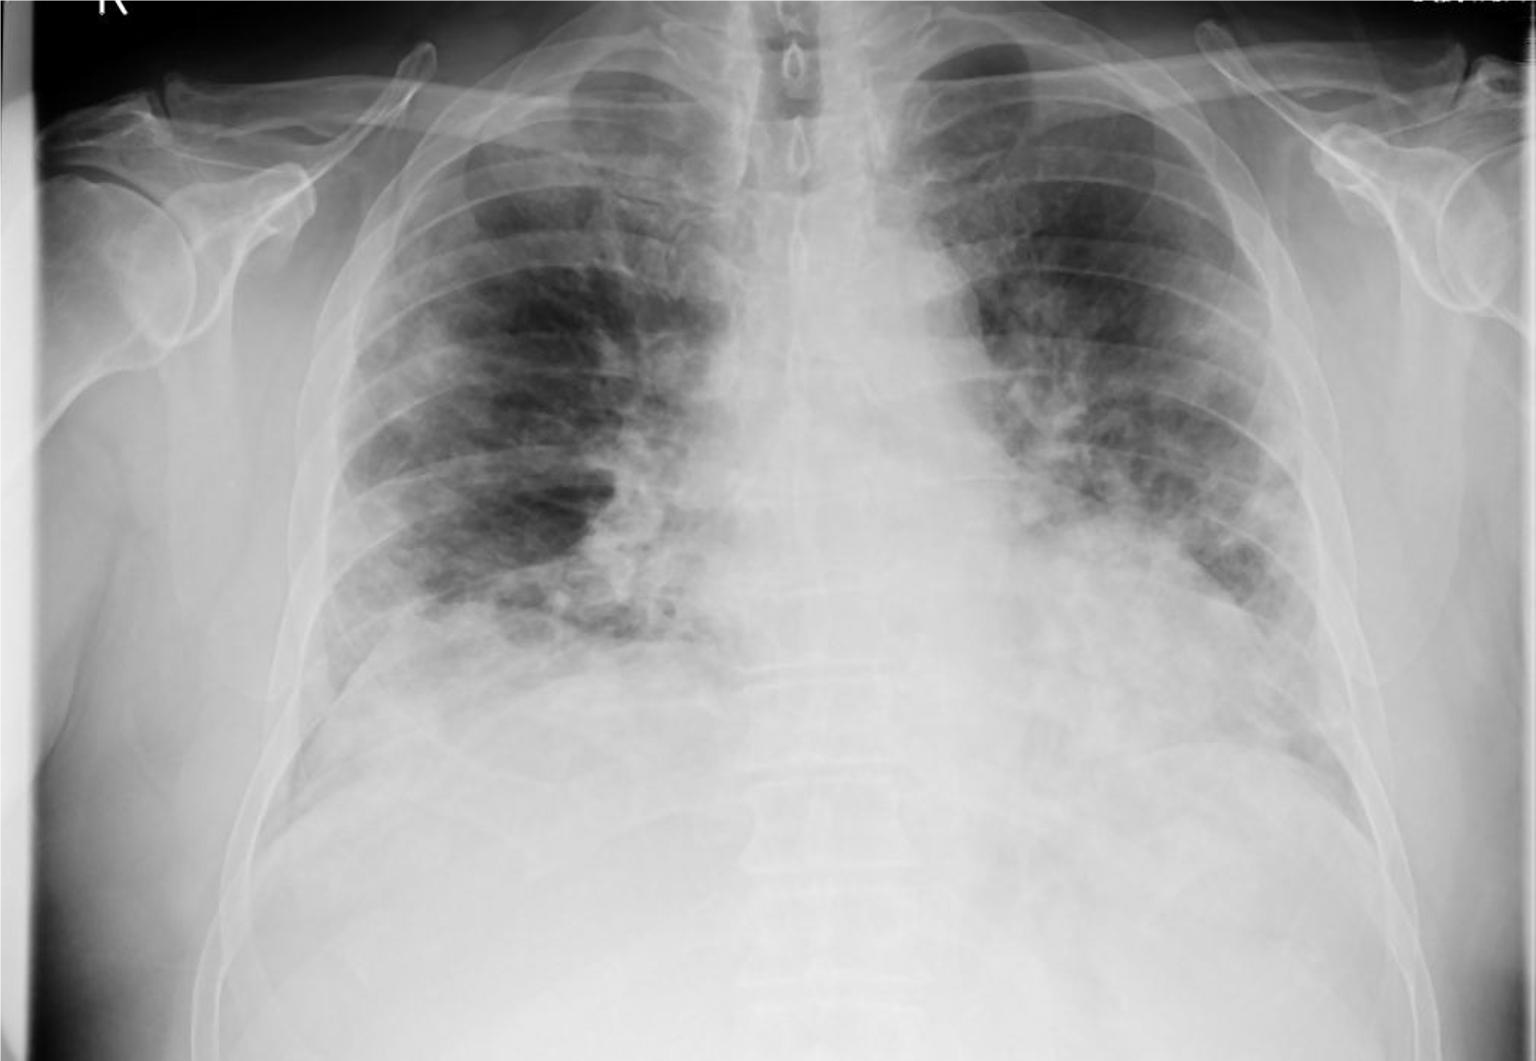

Prof. Dr. Alexander Jesser betreute gemeinsam mit seinem Mitarbeiter Roman Radtke die Studentin bei ihrer vielversprechenden Forschungsarbeit. Prof. Jesser erläutert: „Bei einer Erkrankung der Lunge ist das betroffene Gewebe meist weniger transparent für die Röntgenstrahlung und kann durch seine Form und Abgrenzung Aufschluss geben, um welche Art der Krankheit es sich handelt. Eine Covid-19-Erkrankung zeigt meist milchglasartige Veränderungen in beiden Lungenflügeln. Ist eine Erkrankung der Lunge durch eine Infektion mit Bakterien erfolgt, ist mehrheitlich nur ein Flügel der Lunge verändert. Eine gleichmäßige Ausbreitung über alle Bereiche der Lunge ist dabei also ein Hinweis auf eine Covid-19 Infektion.“

Zur automatisierten Auswertung werden die Aufnahmen in einen Standard-PC eingelesen und mit einer speziellen mathematischen Operation der Kontrast erhöht – ein Vorteil bei qualitativ schlechten Aufnahmen, die mit älteren Röntgenanlagen entstehen. Die Software erstellt neben einem Falschfarbenbild, das die Auswertung vereinfachen kann, ein Binärbild, auf welchem sich bereits die Umrisse der Lunge sowie Spuren von geschädigtem Gewebe erkennen lassen. Durch einen weiteren Algorithmus werden die im Binärbild vorhandenen Kanten und Grenzen der einzelnen Bereiche ermittelt. Die Software kann durch weitere Berechnungen Flächen- und Symmetriebetrachtungen vollziehen und anhand dieser mit großer Wahrscheinlichkeit zwischen bakterieller- oder viraler Lungenentzündungen unterscheiden.

Einseitige Veränderung einer Lunge, hervorgerufen durch eine bakterielle Lungenentzündung. Foto: HHN